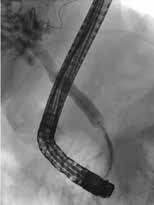

Obstruksjon av pankreas hovedgang Årsaken til smerter ved kronisk pankreatitt er multifaktoriell men kan hos mange, spesielt i tidlig fase av tilstanden (før pasienten blir opiatavhengig), forklares helt eller delvis av økt trykk i pankreas hovedgang på grunn av obstruksjon av fløde av pankreassaft. Obstruksjonen er oftest forårsaket av strikturer og konkrementer i caput eller collum og gir dilatasjon av hovedgangen. Obstruksjon lenger oppstrøms i corpus og cauda har sjeldnere klinisk relevans. Den vanlige og minst invasive tilnærmingen er å plassere en plaststent forbi obstruksjonen i hovedgangen som trykkavlastning for å se om dette bedrer smertene. Dersom effekt kan man fortsette stentbehandling og evt. gå videre med andre invasive tiltak. ESGEs retningslinje fra 2018 foreslår endoskopisk terapi og/ eller ekstrakorporal sjokkbølge-litotripsi (ESWL) som førstevalg for smertefull, kronisk pankreatitt med obstruerende konkrement og dilatasjon av hovedgang i caput eller corpus. Imidlertid viste ESCAPE-studien fra 2020 og en senere langtids oppfølgingsstudie at tidlig (opiatavhengighet < 6 mnd.) kirurgi var bedre enn endoskopisk behandling i å gi smertelindring både på kort og lang sikt. Pasienter operert tidlig hadde også mindre reintervensjoner enn pasientene med endoskopisk behandling. Nyere retningslinjer fra ASGE (2024) anbefaler derfor tidlig MDT vurdering med tanke på kirurgi. Det er imidlertid mange faktorer som påvirker valg av terapi, inklusiv pasientens ønske, komorbiditet og alder, og all invasiv (endoskopi/kirurgi) behandling har dårligere effekt jo lenger ut i sykdomsforløpet man har kommet. Tidspunkt for intervensjon kan være like viktig som valg av prosedyre, og beslutning om valg av terapi krever ekspertise og nøye risikovurdering i hvert enkelt tilfelle. All endoskopisk intervensjon på pankreas er beheftet med komplikasjoner som post-ERCP pankreatitt, blødninger, perforasjon og infeksjon. Pasienter med kronisk pankreatitt har dessuten økt risiko for adenocarcinom i pankreas som er en viktig differensialdiagnose ved dilatasjon av pankreas hovedgang eller forverring av symptomer hos pasienter med kronisk pankreatitt.

Små konkrementer i pankreas hovedgang (< 5 mm) kan ofte fjernes endoskopisk ved at strikturer dilateres og konkrementet hentes

ut med konvensjonelle metoder (Fig 4). Større konkrementer er mer krevende og kan behandles med ESWL eller pankreatikoskopi og fragmentering av konkrement(ene) med sjokkbølgelitotripsi eller laser. Selv om man tilsynelatende klarer å fjerne alle konkrementer fra hovedgangen er tilbakefallsfrekvensen høy og pasientene risikerer langvarig stentbehandling (vanligvis en eller flere plaststenter) og gjentatte endoskopiske prosedyrer.

Standard behandling av benigne strikturer har vært ERCP med gjentatte dilatasjoner og innleggelse av multiple plaststenter i gallegang over en periode på ett år (Fig 5). De senere år har bruk av selvekspanderende metallstent i 6-12 mnd. blitt mer vanlig dersom forholdene teknisk ligger til rette for dette. Det er imidlertid risiko for residiv av striktur på grunn av progresjon av grunntilstanden så gjentatt endoskopisk behandling kan bli nødvendig.